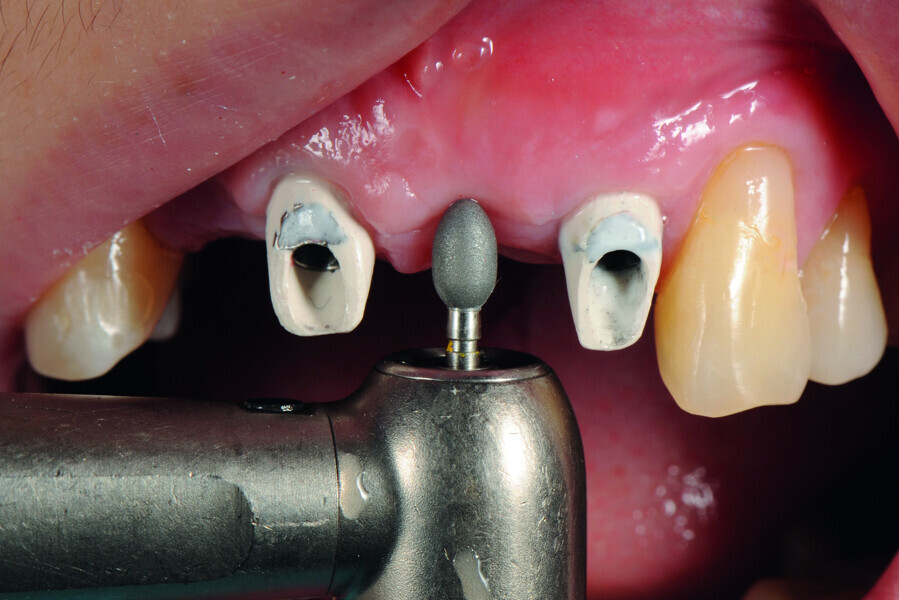

Fig. 15: Insertion of provisional abutments.

Fig. 16: Modification of the gingival contour under the pontic.